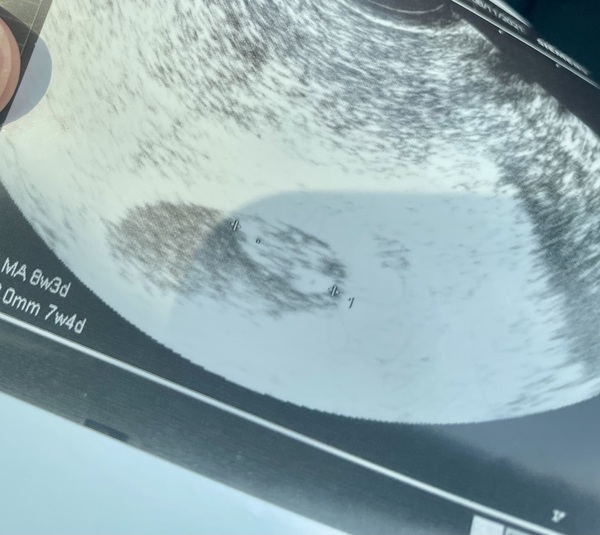

Sean and I found out just one week ago at our 11 week scan that our baby stopped growing at just 7 weeks and 4 days, and it’s little heart had now stopped beating.

We first learned something might be wrong when we went to our first ultrasound at 7.5 weeks. I was surprised to see how tiny the baby looked on the ultrasound, and we were told it was measuring one week behind. Although there was a strong heart beat.